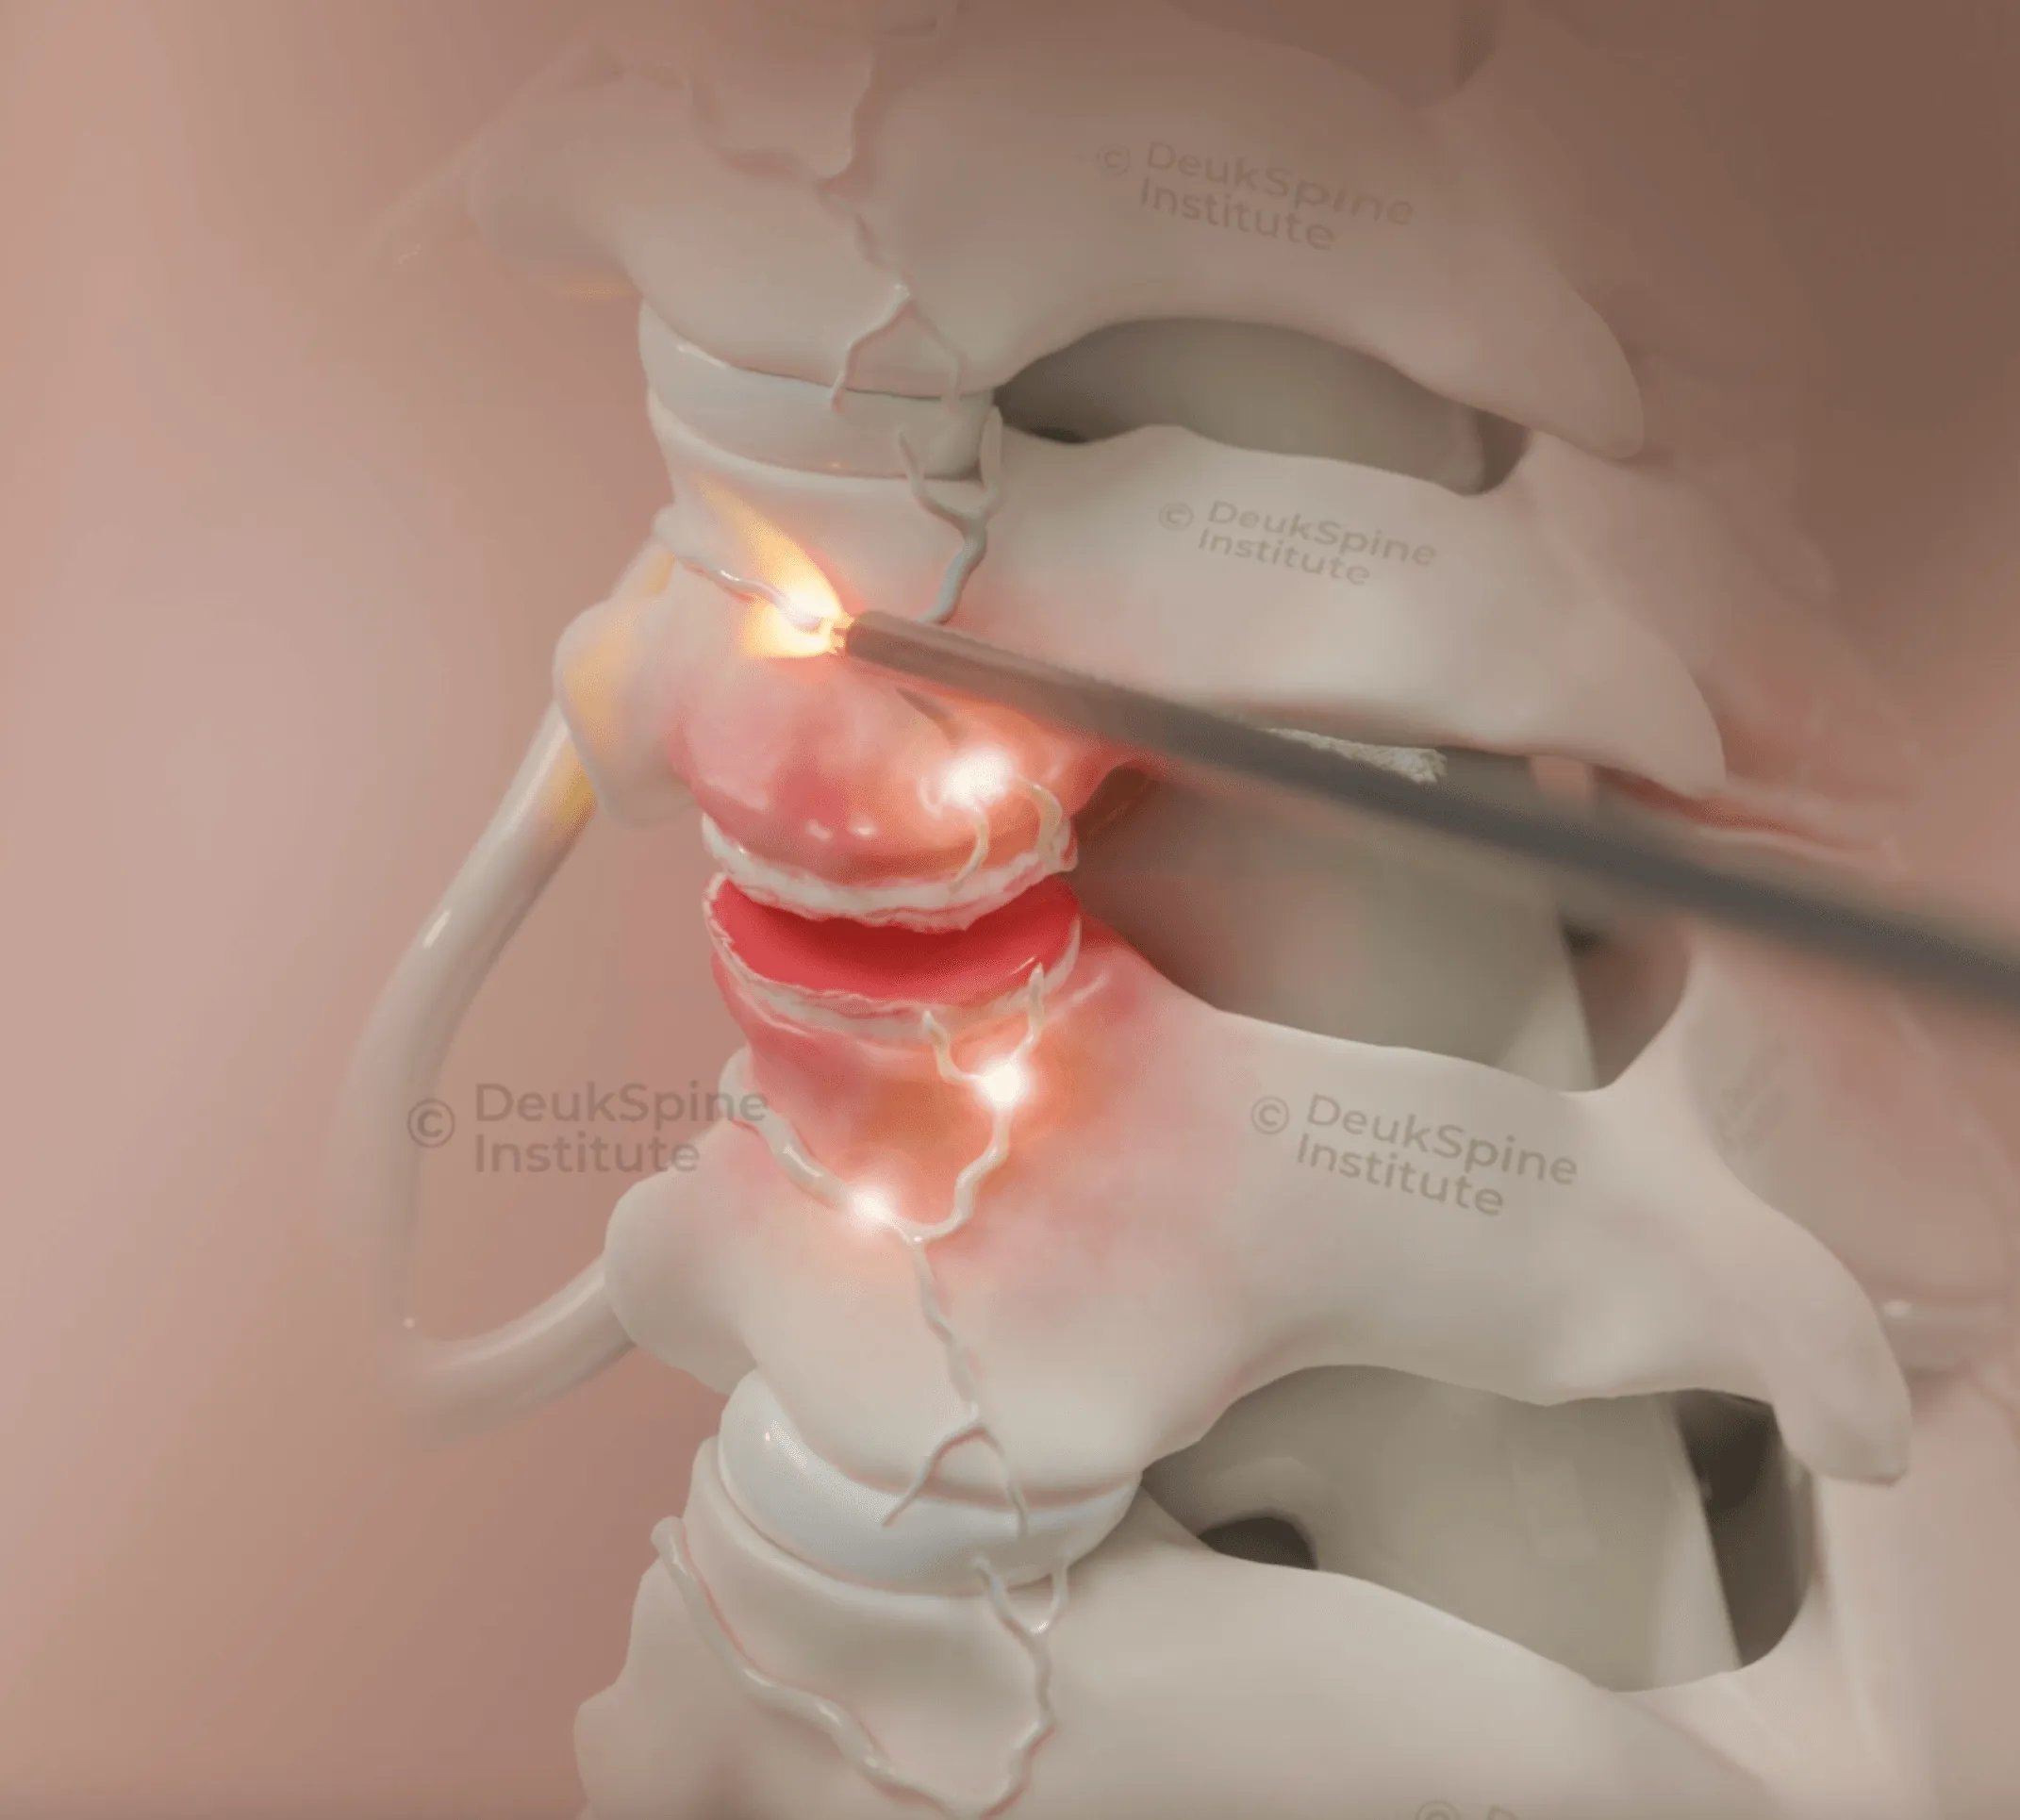

This is a state-of-the-art, arthroscopic procedure performed by Dr. Deukmedjian. Using an advanced endoscope and a half-millimeter-wide laser, the surgeon accesses the damaged disc through a tiny incision, avoiding muscle damage. The Deuk Spine Institute offers:

- A Precision Cure: The laser vaporizes and removes the damaged, inflammatory disc material and fragments that are causing the pain. We can see the nerves and spinal cord directly, ensuring an extremely safe treatment.

- Unmatched Success: The DLDR® treatment has the highest success rate of all treatments discussed: a 99% cure rate for neck pain coming from a herniated disc.